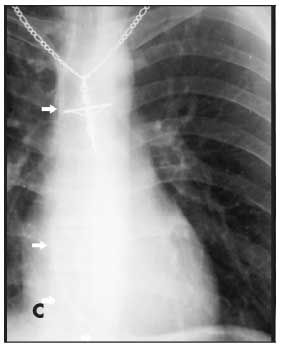

Figures B, C, and D are from a 17-year-old boy with Ewing sarcoma of the left hemipelvis. Fluoroscopy was used to confirm catheter placement, and blood return and ease of flushing the catheter were verified. During a routine clinic visit 18 months later, the patient complained of a cough and “feeling funny.” A chest radiograph was read as normal. A CT scan of the chest, obtained for routine evaluation of possible metastasis, was also interpreted as normal. However, embedded in the radiologist’s report was the comment, “A unipolar transvenous pacemaker has been placed with its tip in the right ventricular apex.” What the radiologist noticed was actually a fractured piece of CVC tubing (Figure B, arrow). Careful inspection of the patient’s earlier “normal” chest radiograph showed the fractured piece of tubing within the right atrium and ventricle (Figure C, arrow). A second chest radiograph showed the tubing fragment lodged in the right pulmonary artery extending into the right lung (Figure D, arrows). No POS was seen in a review of the patient’s radiographic records.

The second case highlights the necessity of careful inspection of all radiographic images ordered and their respective reports. The “funny feeling” the patient had been experiencing may have been related to cardiac arrhythmias caused by stimulation of the right ventricle by the detached tubing fragment.